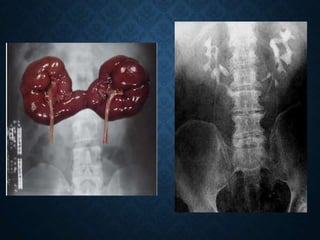

ANOMALIAS DE FUSION

Fusion renal en la pelvis

1/600-1/800 nacimientos

Hay aumento de la

incidencia:

• Obstrucción

• Litiasis

• Infección

• Aneurisma abdominal

• Tumor de willms

RIÑON EN HERRADURA

ANOMALIAS DE FUSION Fusionrenal en la pelvis 1/600-1/800 nacimientos Hay aumento de la incidencia: • Obstrucción • Litiasis • Infección • Aneurisma abdominal • Tumor de willms RIÑON EN HERRADURA